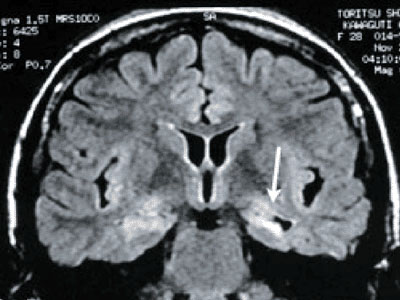

てんかんの原因となりうる大脳の形成障害や脳腫瘍などがないか、MRI、CT、SPECT、PETなどの検査を行います。

↑側頭葉てんかんの「海馬硬化症」